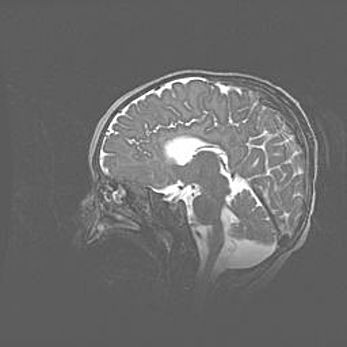

Аномалия Денди-Уокера. Признаки гипоплазии мозолистого тела.

Возраст: 5 месяцев 3 дня

Вес: 5550 г

Пол: мужской

Окружность головы: 39 см

Срок гестации: 40 недель

Аномалия Денди-Уокера – это порок развития головного мозга, для которого характерна триада симптомов: гипотрофия или аплазия червя мозжечка и/или полушарий мозжечка, расширение четвёртого желудочка с формированием ликворной кисты задней черепной ямки, гипертензионная гидроцефалия различной степени.

Гипоплазия мозолистого тела относится к дефектам внутриутробного этапа развития мозговой ткани, возникающим в процессе закладки структур головного мозга, что происходит на начальных этапах развития эмбриона.